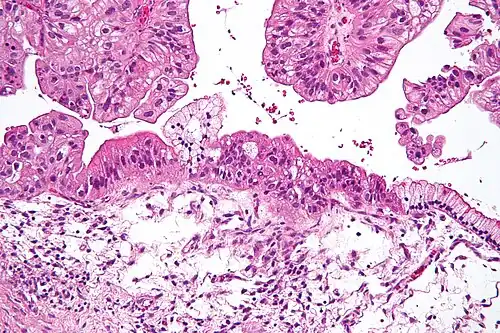

| Intermediate magnification micrograph of a low malignant potential (LMP) mucinous ovarian tumour. H&E stain.

The micrograph shows: Simple mucinous epithelium (right) and mucinous epithelium that pseudo-stratifies (left - diagnostic of a LMP tumour). Epithelium in a frond-like architecture is seen at the top of image. | |